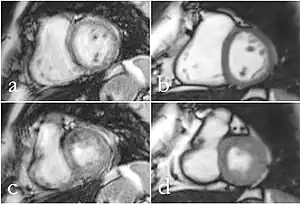

Although applications of real-time MRI cover a broad spectrum ranging from non-medical studies of turbulent flow[26] to the noninvasive monitoring of interventional (surgical) procedures, the most important application making use of the new capabilities is cardiovascular imaging.[1] Previous cardiac MR (CMR) used cine techniques to capture the periodic motion of the heart. However, this is not feasible for patients with arrhythmia, where the cardiac cycle is unpredictable.[27] With the new method it is possible to obtain movies of the beating heart in real time with up to 50 frames per second during free breathing and without the need for a synchronization to the electrocardiogram.[28] A study performed by Laubrock et al.[27] demonstrated that RT-MRI produced higher quality images with a higher SNR than cine CMR with a bSSFP sequence and radial k-space sampling. RT-MRI also removes the need for breath-holding while imaging, leading to a more comfortable experience for the patient as well.[27]